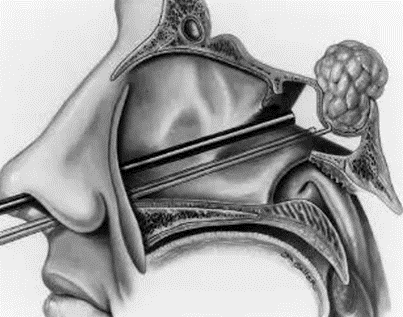

垂体瘤的治疗大多数的最佳方案为内镜经鼻手术。鼻腔属于耳鼻喉科范畴,术后需要耳鼻喉医生了解鼻腔粘膜修复情况,鼻腔是否通气、是否有鼻窦炎,是否有脑脊液漏,是否会头痛等情况。根据具体情况,耳鼻喉科医生会清理鼻腔、内镜观察、药物治疗,并制定下次复诊的时间。

垂体瘤手术主要由神经外科医生完成。术后复查,神经外科医生需要了解患者术后恢复情况、鼻腔改善情况、内分泌情况、视力视野恢复情况等。了解是否有残留、复发,并且决定下一次复查的时间。如果发现有复发,给出专业建议,观察、放疗还是再次手术治疗。